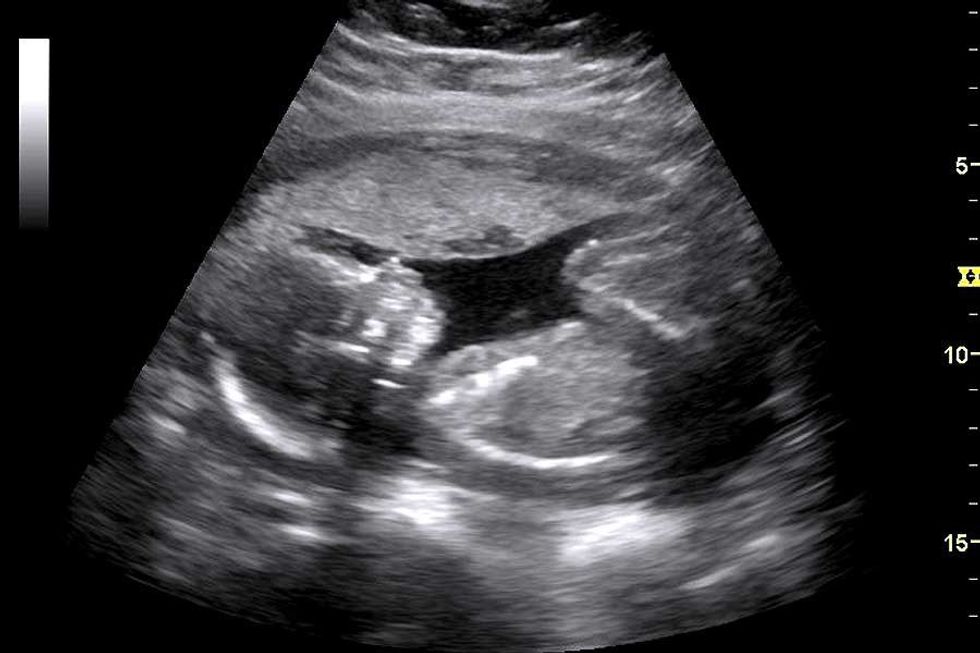

First off, I want to start out by saying how appalling this is. If you have not seen about the Ohio abortion bill passed, it states that you cannot have an abortion after a heartbeat is detected. A heartbeat is detected around 6 weeks, a month and a half into a pregnancy. Most women don’t find out they’re pregnant until about 6-8 weeks, or their second missed period. This law basically takes away abortion completely since most women won’t have enough time, or any time, to make a decision after finding out they’re pregnant. That being said, the bill also does not make any exceptions for victims of rape or incest. The only exception is to save the life of the mother.